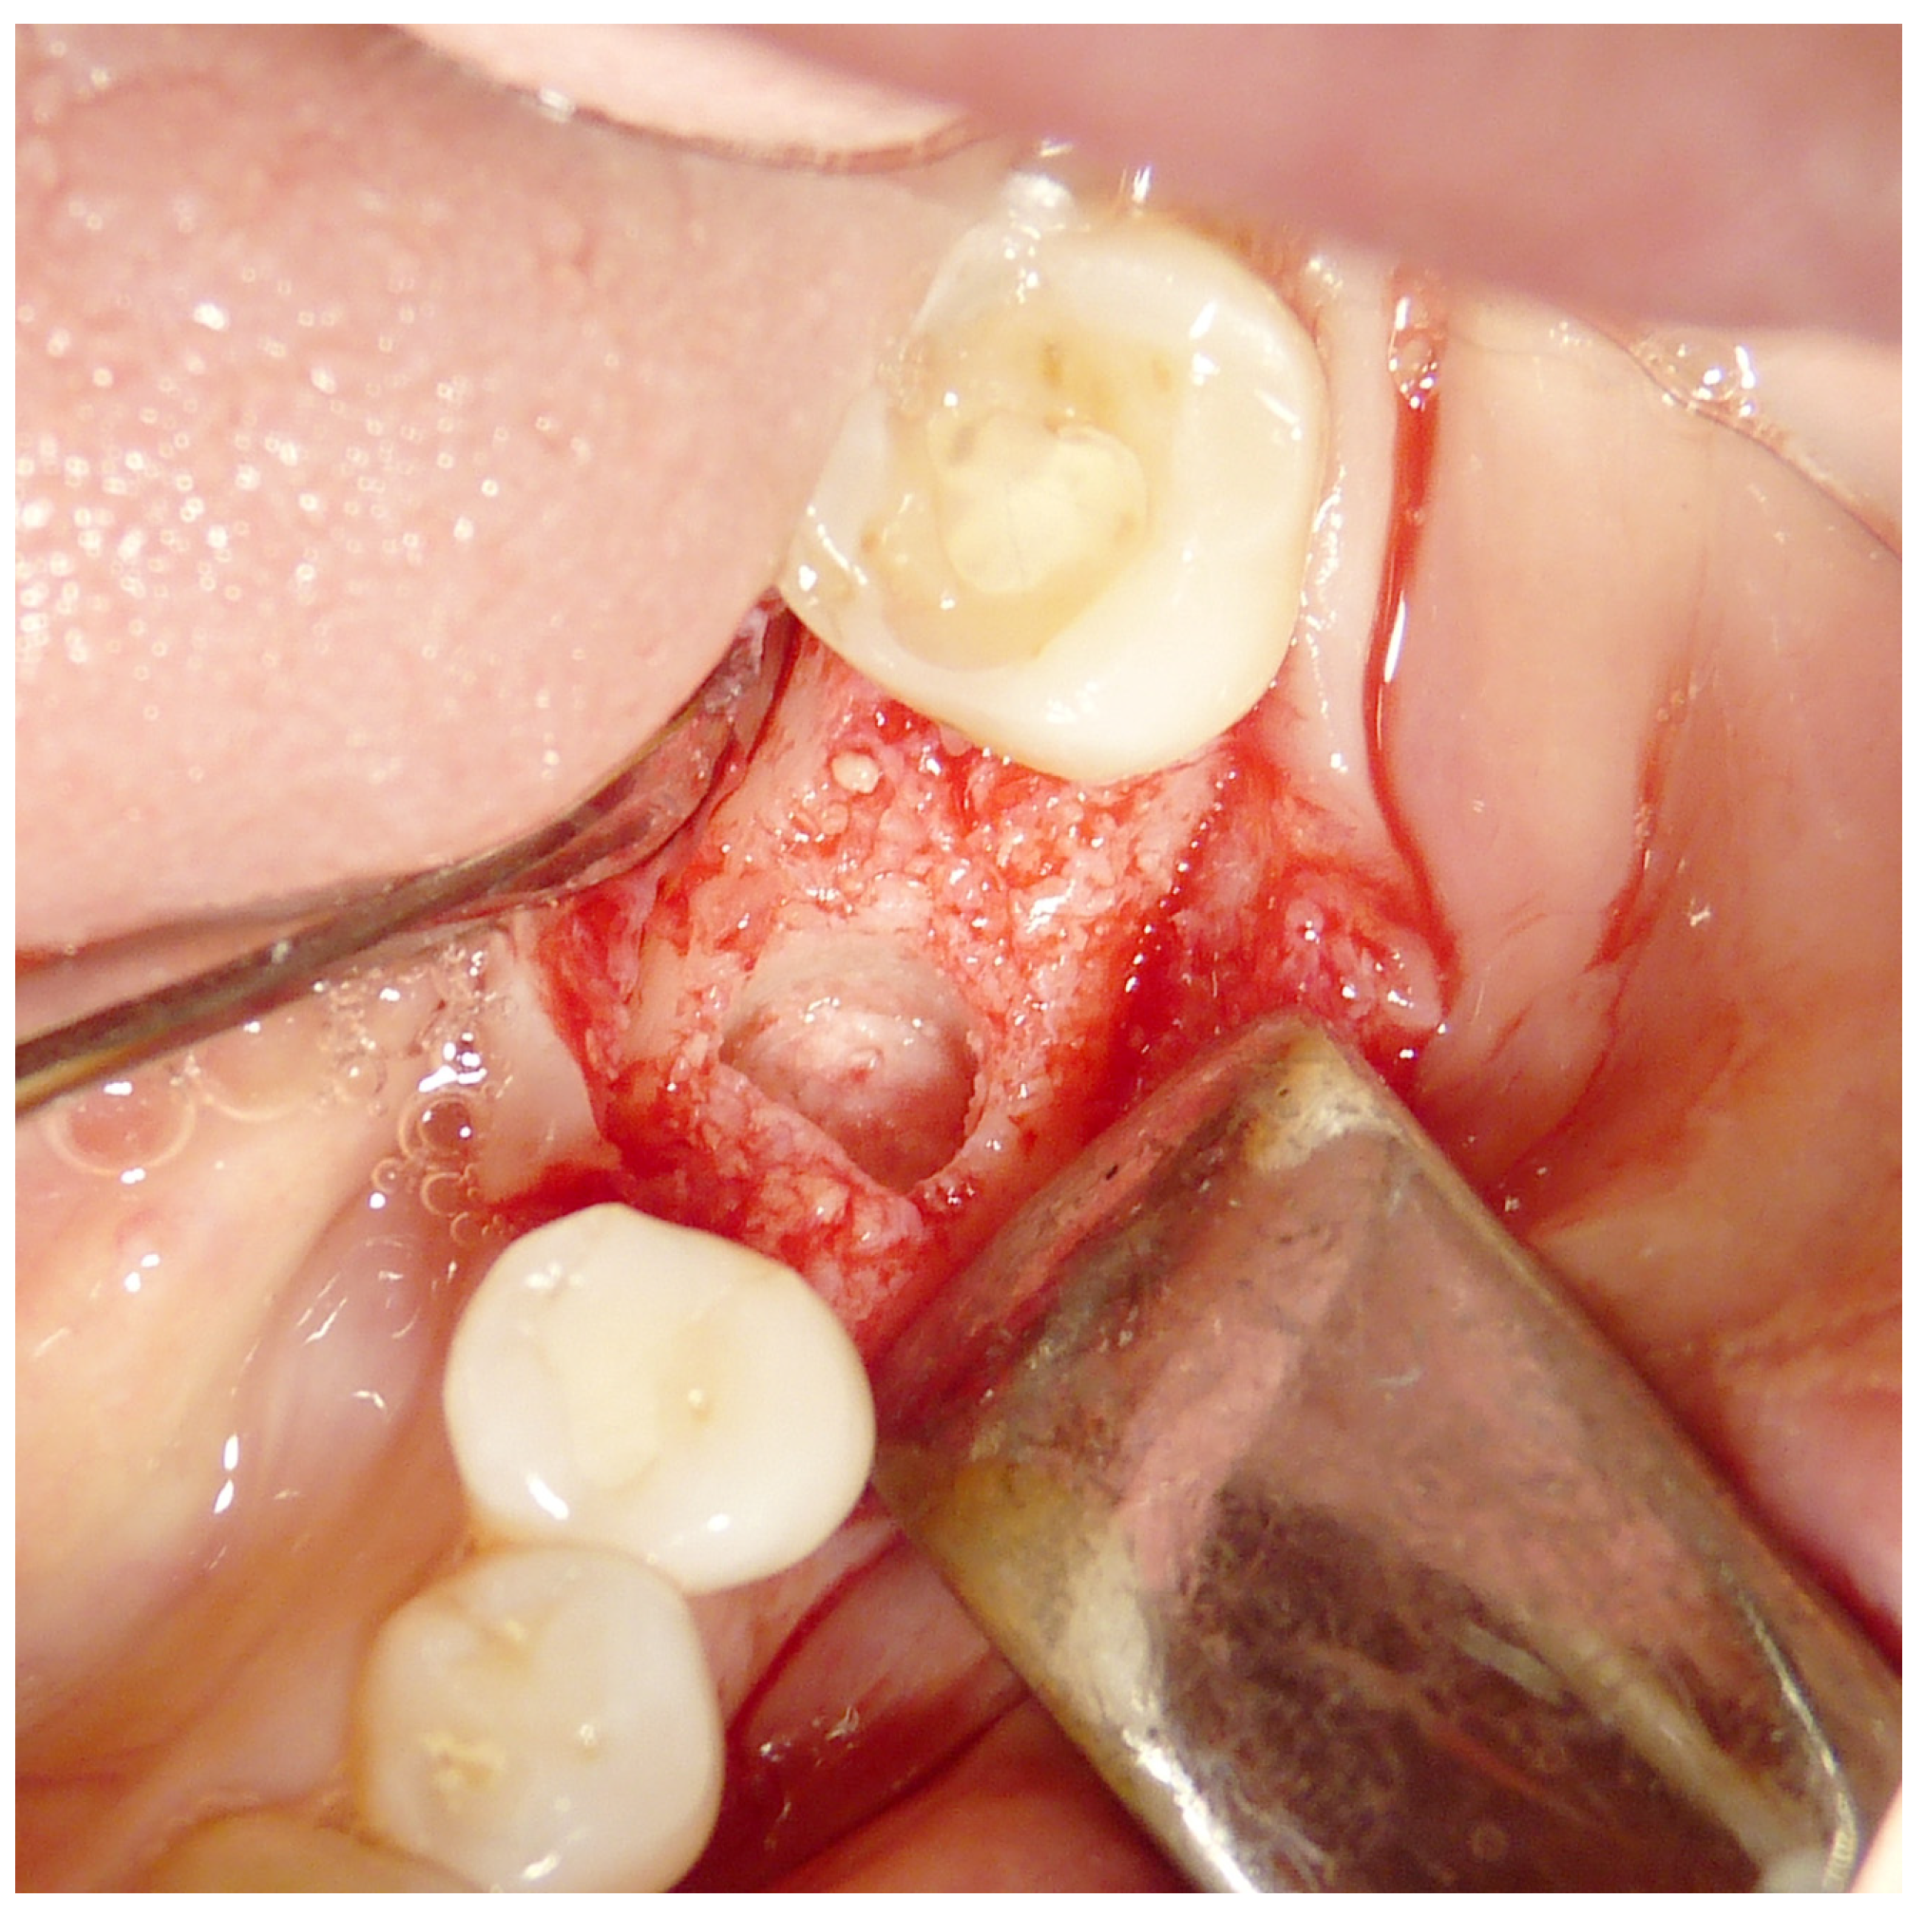

Both hard and soft tissues remained steady throughout the healing process. There were no difficulties with the soft tissue grafting treatments’ healing. After a healing period of 4 months, seven biopsies (Figure 2 and Figure 3) were performed during the implant insertion procedure; after the healing period (8 months after the socket preservation procedure), seven biopsies were performed (Figure 4 and Figure 5).

Figure 2.

First histology after 4 months healing.